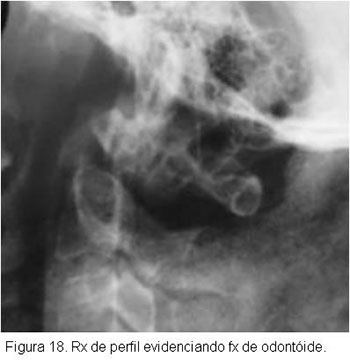

No estudo radiográfico, nas fraturas sem desvio, seja na projeção ântero-posterior, seja na de perfil, apenas se verá o traço de fratura do dente do áxis, e nas fraturas com desvio será vista a fratura com desvio do fragmento distal e o escorregamento do atlas. Nas fraturas sem desvio por vezes é muito difícil que se veja o traço de fratura, só sendo possível o diagnóstico pela tomografia.

Ainda quanto ao diagnóstico radiológico das fraturas sem desvio deve-se acrescentar que carece haver cuidado especial com as crianças, quando ainda não ocorreu ossificação completa da vértebra.Radiologicamente, na criança, o dente e o corpo do áxis estão separados por uma faixa de tecido transparente ao raio X, que progressivamente vai estreitando, até desaparecer aos 10-11 anos, quando o dente e o corpo do áxis se fundem, o que raramente não se completa em idades maiores. A não fusão do dente do áxis pode simular uma fratura sem desvio. Os pacientes com fratura do dente do áxis freqüentemente têm queixas pobres, apenas de cervicalgia pouco intensa e certa dificuldade para a movimentação do pescoço, não raramente procurando tratamento vários dias depois do acidente. Algumas vezes procuram tratamento referindo dor violenta, grande dificuldade à movimentação e suportando a cabeça com as mãos. Sinais neurológicos só aparecem numa pequena minoria (Figuras 18,19 e 20).